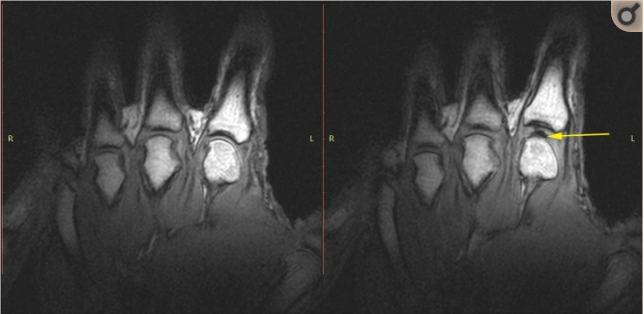

The last reason, and probably the most common, is the good ol’ gas bubbles. This is what you hear when you crack your knuckles, or when a chiropractor or physical therapist manipulates your spine. There is controversy surrounding this topic. The prevailing theory for years was that a bubble of gases inside the joint pops or collapses, causing the sound. This is called cavitation and is said to give you a sudden increase in mobility. A study in 2015 by Kawchuk et al. found just the opposite. Through real time MRI, they were able to conclude that the sound is actually the formation of a bubble when the joint is stretched, rather than a collapse. There is a substance called synovial fluid that is inside the joint and has an adhesive property. When force is applied to the joint that is stronger than the adhesion, the fluid fractures and causes a cracking sound. This is called tribonucleation. The idea here is that when the joint separates, negative pressure is formed and pulls dissolved gases out which form a bubble.

Kawchuk et al., 2015